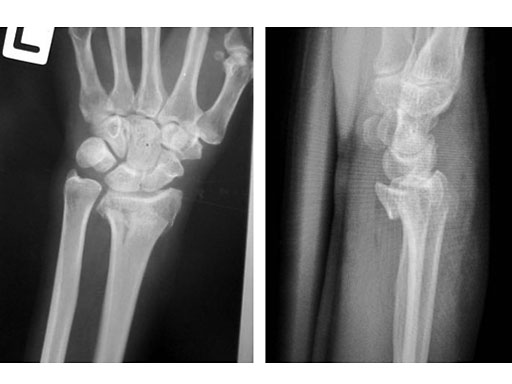

Fig 2a-b Post-op immediate